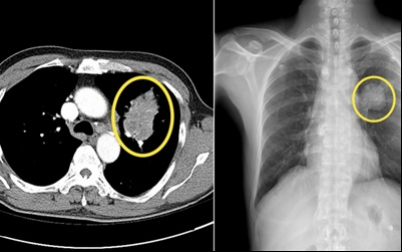

10. 폐암 초기 증상 - 상대 정맥 증후군

상대정맥 주위에 폐암이 생겨 상대정맥을 압박할 때 생기는 증상을 말합니다 . 혈액 순환 장애가 생겨 머리와 팔이 심하게 부어 오르고 호흡 곤란 , 가슴 정맥 돌출 등의 증상이 발생할 수 있습니다 .